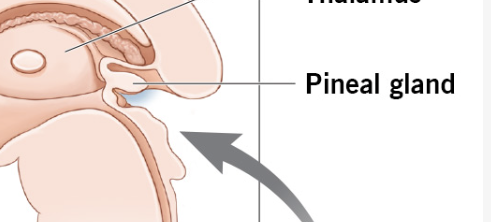

Which Diencephalon structure contains the Pineal Gland(secretes Melatonin)

Epithalamus

This region of the diencephalon helps to regulate the human circadian cycle (24-hour cycle).

It’s the Pineal Gland